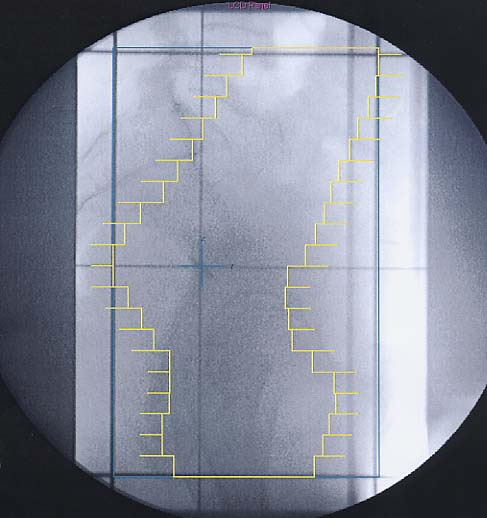

Gynäkologische Tumore des Beckens: Simulationsbild